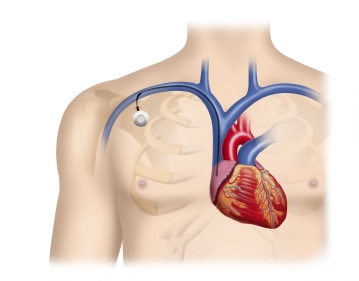

Postoperativ erfolgt zusammen mit dem Ausschluß eines Punktionspneumothorax die röntgenologische

Verifizierung der korrekten Lage des Portsystems auf einer Thoraxübersichtsaufnahme.